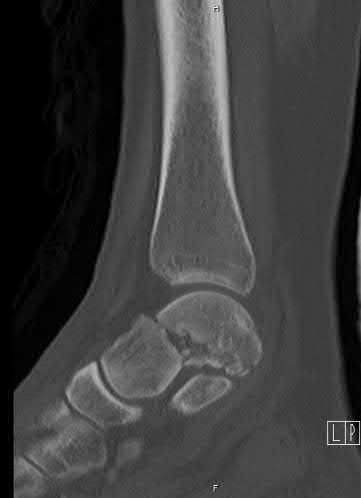

A 28-year-old male sustains a severe hyper-dorsiflexion injury to his ankle in a motor vehicle accident, resulting in a Hawkins Type III talar neck fracture. Which of the following arteries provides the predominant blood supply to the body of the talus, placing it at significant risk for avascular necrosis in this injury?

Correct Answer: Artery of the tarsal canal

Explanation:

The artery of the tarsal canal, which is a branch of the posterior tibial artery, provides the dominant blood supply to the talar body. In a Hawkins Type III fracture (talar neck fracture with subtalar and tibiotalar dislocation), the blood supply from the artery of the tarsal canal, the artery of the sinus tarsi, and capsular vessels are disrupted, leading to an avascular necrosis (AVN) rate approaching 100%.